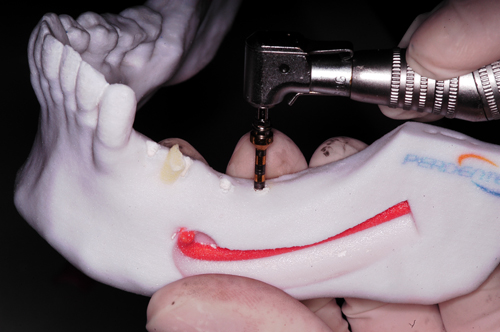

Palabras Clave: ELG: Estereolitográfico OH: Oclusión Habitual ORC: Oclusión en Relación Céntrica Paciente de 35 años de edad ,sexo masculino que lo derivan para implantar el tercer cuadrante. A la auscultación presenta ruidos articulares de tipo chasquido que remiten temporalmente luego de limitación de apertura bucal y maniobras quinesiológicas distractoras. También se observan recidivas de caries en algunos empastes y falta de disclusión canina de ambos lados. Se estudia el caso desde un punto de vista clínico, scanografico mediante Dentascan y tridimensional mediante montaje en articulador. A partir del scanner se obtienen datos para confeccionar modelo estereolitográfico (ELG),operar en el y construir férula quirúrgica dento-muco soportada. Habitualmente se procede directamente a implantar, dado que ese era el requerimiento del profesional derivante y el deseo del enfermo. Sin embargo, esa actitud enmascararía otro tipo de problemas que la boca presenta. Se consulta al odontólogo derivante, y coincide con mi opinión acerca de que si solo se lo implanta, sin corregir la posición mandibular, la situación de las ATMs, los empastes sin anatomía y la falta de disclusiones, el resultado final no será el deseado y su eficacia masticatoria no funcionará optimamente. Consultado el paciente coincide y acepta ese concepto y entonces procedemos a confeccionar un Jig de Lucia a partir del montaje de estudio, y lo dejamos puesto en boca toda la noche anterior a la consulta, para proceder a realizar un ajuste oclusal al día siguiente sin engramas anteriores, lo que facilita no tener que relajar nuevamente con laminillas de Long. En esta etapa pierde el implante correspondiente a la pieza 4.7 que traía en boca. Estabilizado el sistema, procedemos a la parte quirúrgica, comenzando por instalar la férula, retirar opérculos gingivales mediante bisturí circular, fresado óseo e instalación de implantes ,toma de impresión a cubeta fenestrada (pegando con metacrilato sin cambios dimensionales, los transfers a la cubeta especialmente diseñada.(1º método de pasividad protética utilizado), e instalación de tornillos de cicatrización. Inmediatamente de retirada la cubeta de boca y colocadas las réplicas de los implantes, procedemos a ferulizar los “ápices” de las réplicas para que no sufran movimientos durante el llenado de la impresión.(2º método de pasividad protética utilizado). Controlamos radiograficamente Tres meses después, procedemos a tomar nuevos registros de arco facial, registros intermaxilares en Oclusión en Relación céntrica, montaje de los modelos obtenidos intra operatoriamente y confección de un conjunto de cuatro coronas provisionales de metacrilato en el sector implantado y las correspondientes al maxilar superior. Verificada la perfecta función de todos los componentes, ausencia de todo tipo de síntoma y comprobada la paz en todo el sistema, procedemos tiempo después a confeccionar las fundas definitivas, que constituyen el “cerrojo” de la dinámica del mismo. Por último, corroboramos la oclusión fundamentalmente en lo que hace a la: